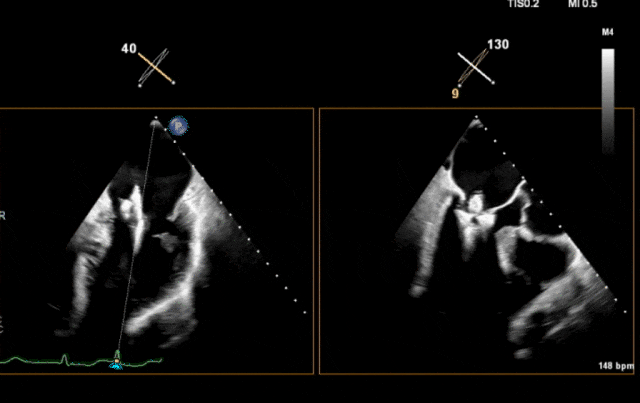

术前超声

图片

术前瓣叶